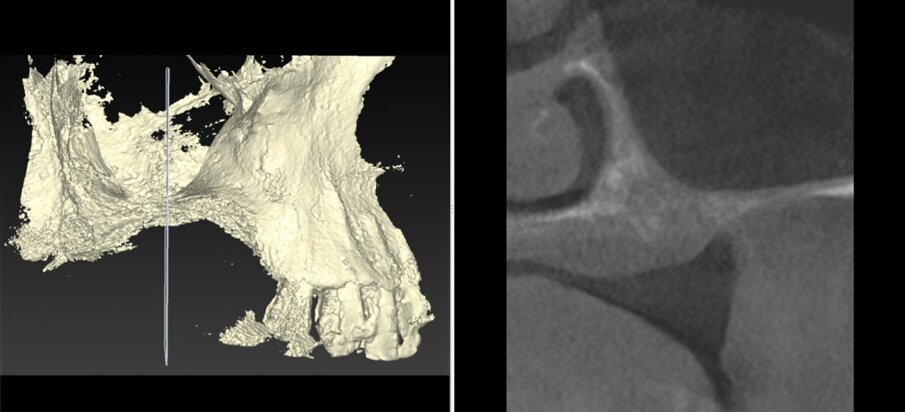

Il piano di trattamento è stato sviluppato utilizzando un flusso di lavoro completamente digitale. Pertanto, i files .DICOM ottenuti dalla CBCT pre-operatoria sono stati utilizzati per generare una ricostruzione 3D del mascellare, che ha permesso di eseguire la progettazione virtuale del volume osseo “ideale” per l’inserimento di 3 impianti in sede #15, #16, e #17. (Figg. 4, 5). Successivamente, è stata creata virtualmente la griglia customizzata corrispondente al volume aumentato nel mascellare della paziente (Fig. 6). Il giorno della chirurgia ricostruttiva (T0), è stata eseguita una profilassi antibiotica (2 g di amoxicillina con acido clavulanico e 500 mg di metronidazolo), una profilassi antinfiammatoria (20 mg di piroxicam), una sedazione cosciente x os (2 ml di delorazepam e 2 ml di diazepam), e disinfezione del cavo orale (risciacquo orale con povidone-iodio per un minuto, perossido di idrogeno per due minuti, e collutorio alla clorexidina 0,2% per tre minuti), e un’anestesia locale mediante articaina 4% contenente adrenalina 1:100.00018. L’esame obiettivo mostra la gravità del difetto osseo che determina un evidente difetto di volume sia in senso orizzontale che in senso verticale (Figg. 7, 8).